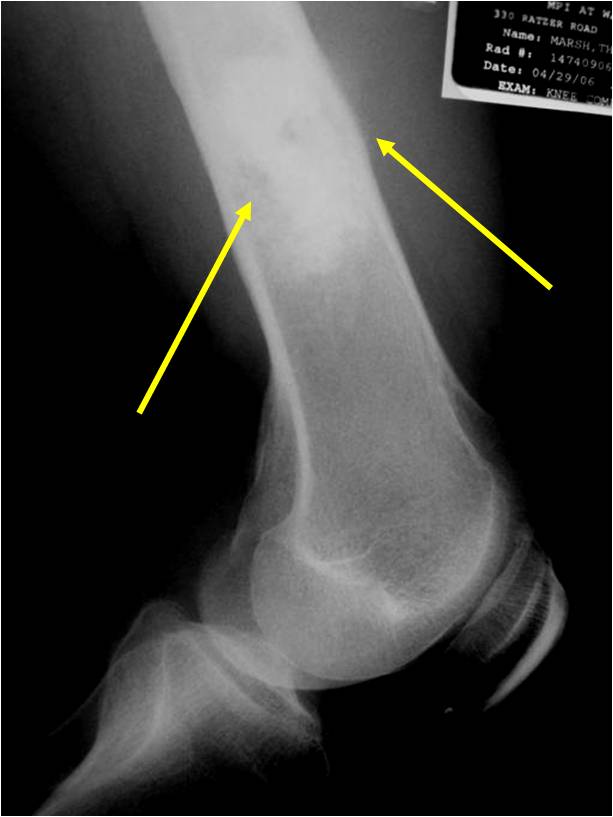

Ill-defined, lytic intraosseous lesion

- Or extraosseous soft tissue mass

- Devoid of calcifications in continuity with lesions having the features of a cartilaginous tumor

Characteristically abrupt transition between chondroid tumor and dedifferentiated, lytic component

Bone may be expanded and adjacent cortex thickened

(Right Arrow)Aggressive Lytic Area (Dedifferentiated Sarcomatous Component) Cortical Destruction Soft Tissue Mass without Calcification